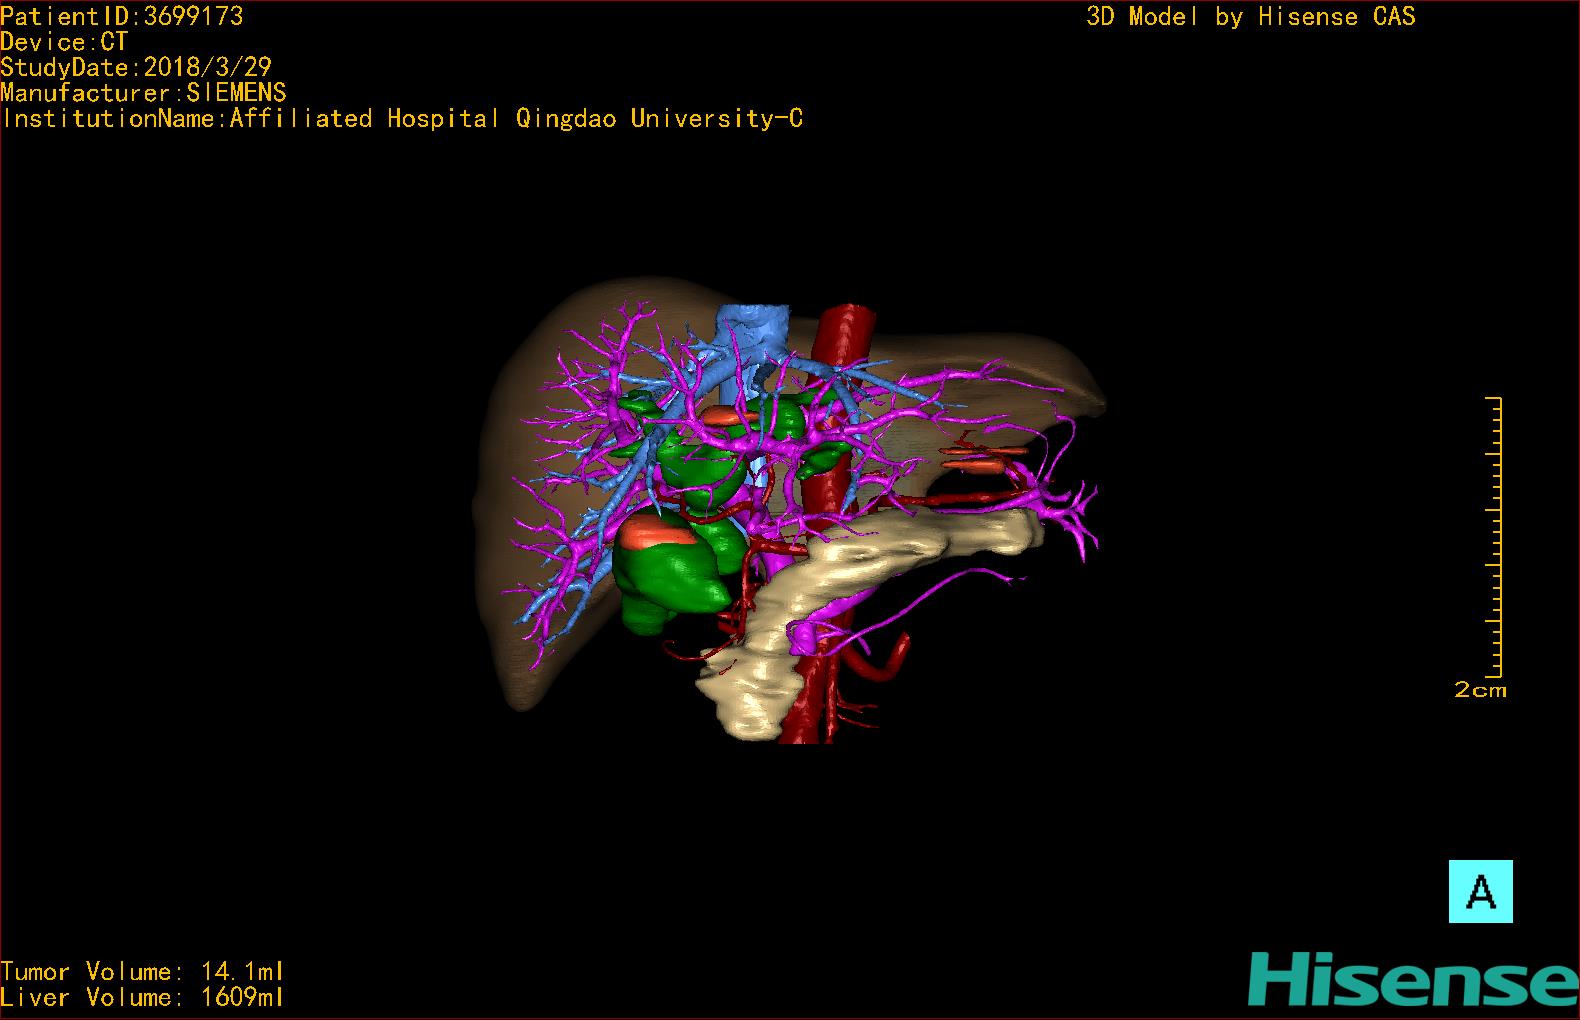

10、三维重建虚拟肝脏、胆道显像技术

三维虚拟肝脏技术是在二维影像学资料如CT等图像的基础上,通过三维重组软件和工具,比如青岛大学附属医院与海信医疗集团联合自主研发的海信计算机辅助手术系统(Hisense Computer Assisted Surgery,Hisense CAS),目前已投入临床并指导实际应用,利用该类系统对二维影像学的数据资料进行三维立体分析,重组形成立体的、有空间结构的、虚拟的肝脏三维图像。这项技术较传统的二维平面成像技术,有着明显的优势,3D虚拟肝脏技术可以构造出一个虚拟的、可视化的肝脏模型。通过对这种模型的观察,可以很容易地分辨出肝脏器官的组织结构、解剖特点,直观研究肝外胆总管的形态差异,明确肝内胆管的形态、走形、是否合并扩张、狭窄及结石,胰胆管合流的形态及共同通道内是否有狭窄、扩张和结石等病变情况,预先规划处理可能合并存在的肝内胆管扩张、狭窄或其他复杂胆道畸形,清晰地显示肝内脉管系统,包括门静脉、肝动脉及肝静脉的走行、分支,并可多角度、全方位观察病变胆道与其周围重要血管尤其是伴行的门静脉之间的解剖关系,大大提高了外科医师在术前对肝脏内部各管道结构及其变异判断的精确性和可靠性,精准地对病变进行判断和评估,还可根据患者自身的病变特点,制定出合理、个体化的手术方案,最大限度地降低术中和术后并发症发生率,并术中导航实时指导手术,提高手术的精准性和成功率。

图12:先天性胆管扩张症梭状型合并左右肝管分别汇入胆总管囊肿三维重建虚拟肝脏、胆道显像

a 图为术前二维CT图像;b 图为CT经多平面重组技术(MPR)所得的三维重建图像,可粗略地判断病变胆管的位置;c 图为MRCP显示胆总管梭状扩张;d 图为术前Hisense CAS三维重建显示胆管的分布走形及其与肝内三套血管系统的解剖关系;e 图为胆道系统立体形态及与肝脏整体的空间关系,箭头处显示对于左右肝管分别汇入胆总管囊肿中,整个肝总管也明显扩张而成为囊肿的一部分。术前规划为先将囊肿完全切除,左右肝管合并成形后再与空肠吻合。